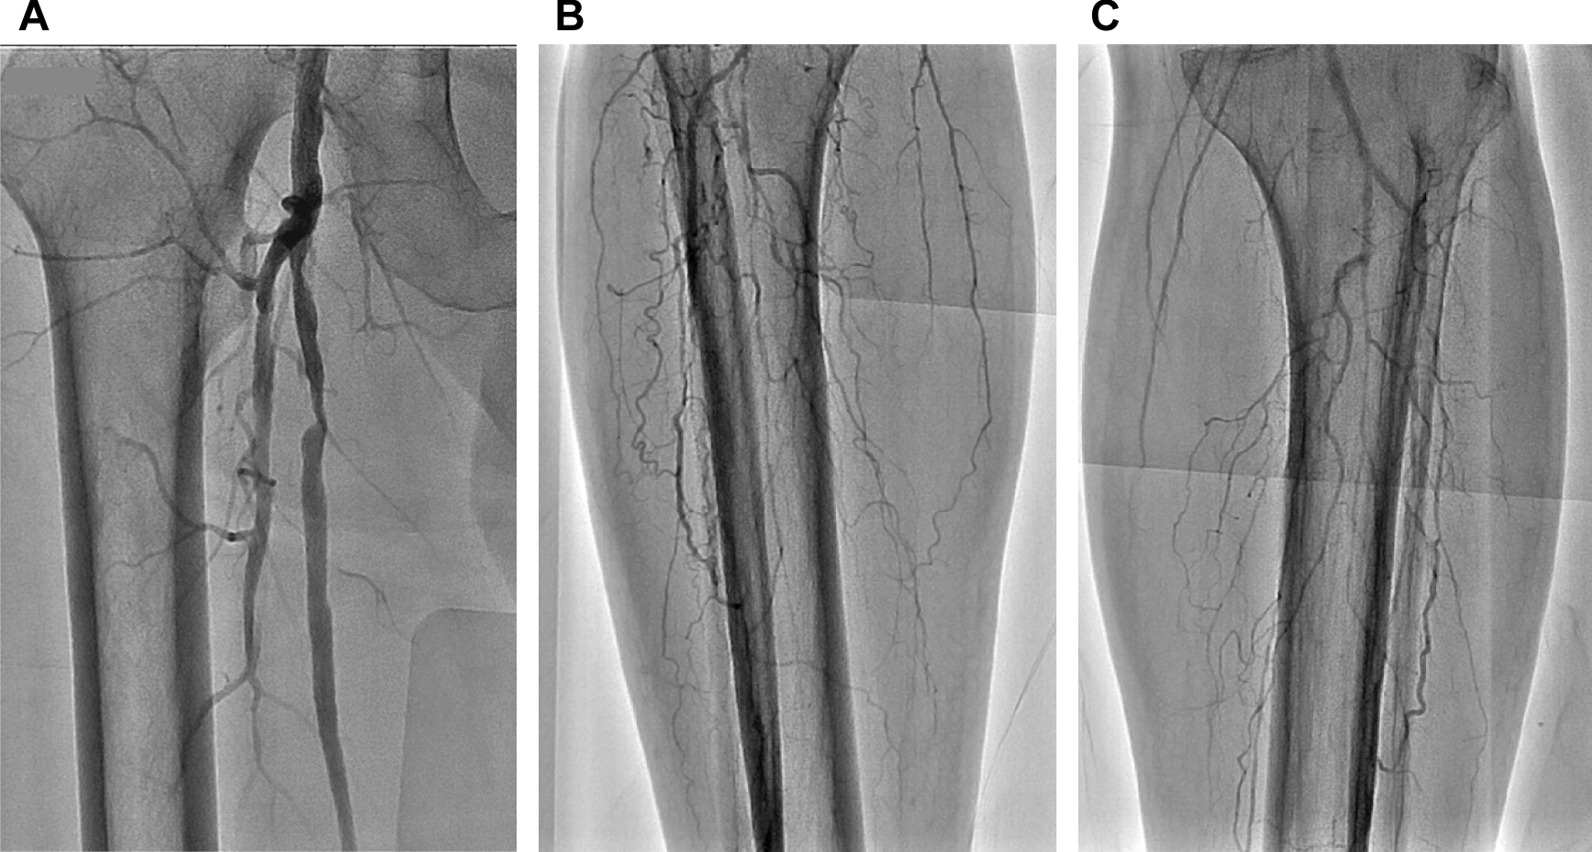

Fig. 7.

Intra-arterial angiography of the lower extremities showing severe stenotic lesions in the right superficial femoral artery (A), occlusive lesions in infrapopliteal arteries in the right lower leg (B) and left lower leg (C)